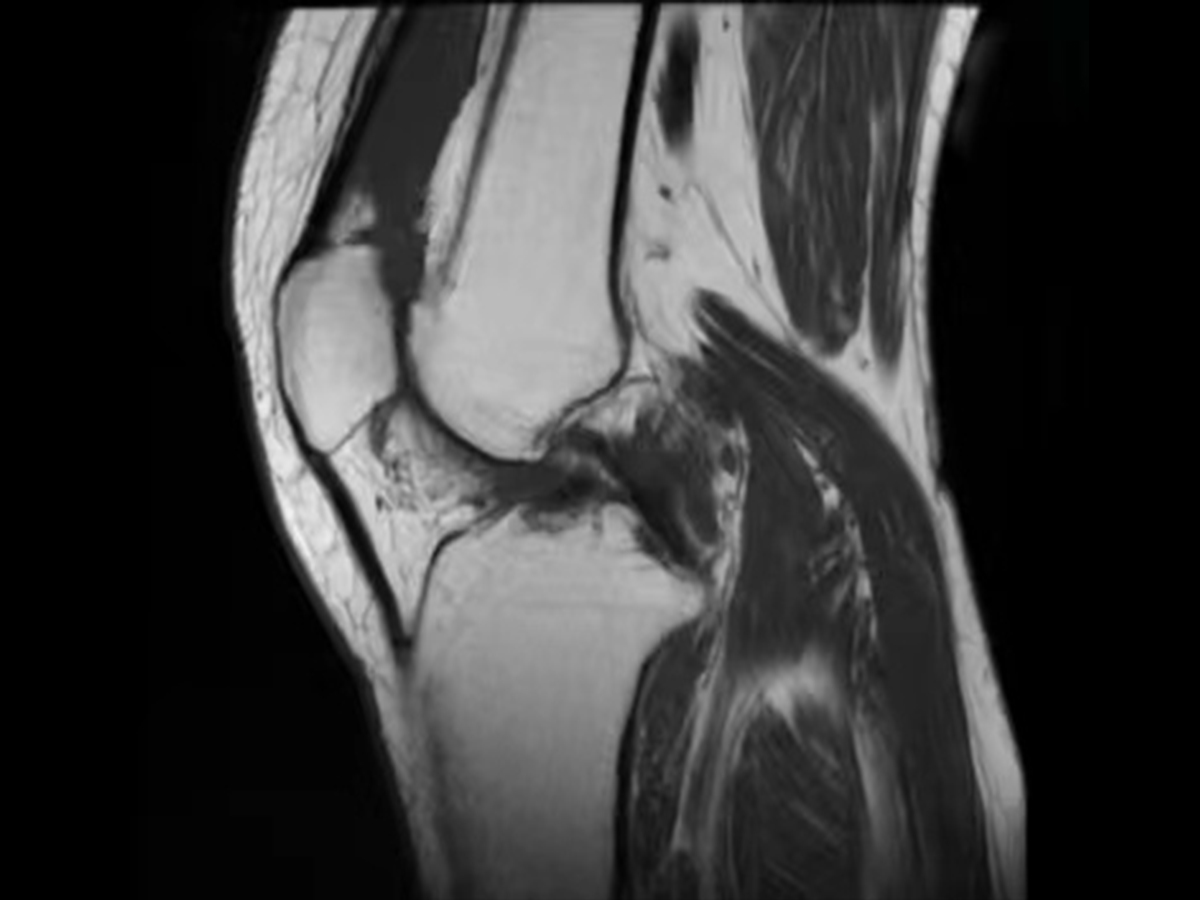

ˋ▽ˊ 年轻人膝盖疼要不要重视?滑膜炎表现及治疗方法大揭秘!接着讲讲西医治疗方法。西医一般会先让你做个检查,像核磁共振啥的,就像给膝盖做个“高清拍照”,看看里面的情况到底咋样。如果确诊是滑... 找到适合自己的治疗方法。只有这样,才能让你的膝盖早日恢复健康,重新活力满满地去拥抱生活。可别让小小的滑膜炎,影响了你的快乐生活啊...